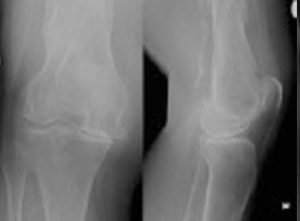

TOTAL KNEE REPLACEMENT

PARTIAL KNEE REPLACEMENT

ASSESSING ADULT KNEE PROBLEMS

MANAGEMENT STRATEGY ADULT KNEE